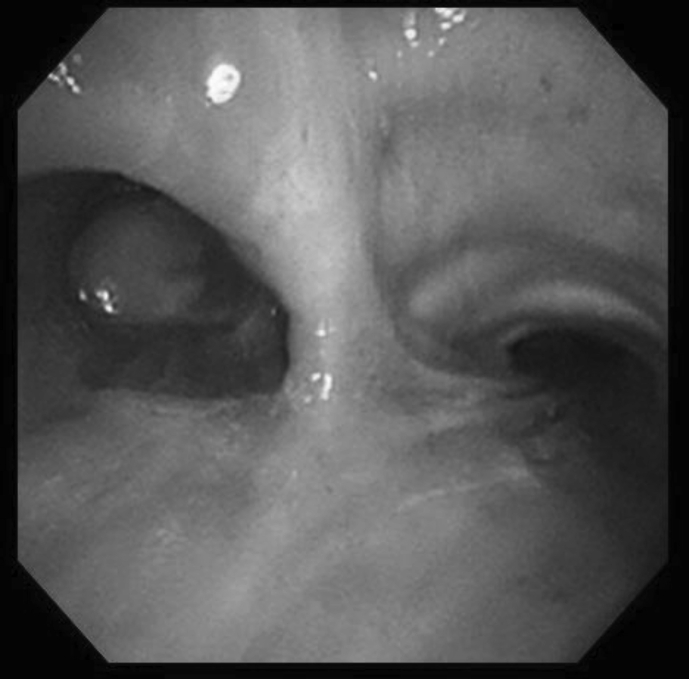

Upon examination, SpO2 was 89% at room air. Laboratory test showed elevated eosinophil count at 651/μL. Additionally, chest radiograph and computed tomography (CT) findings revealed complete collapse of the left lung with hyperattenuated mucoid (HAM) impaction (Fig. 2). Bronchoscopy showed a white, rubbery, thick mucus plug in the left main bronchus, which could not be removed by forceps or suction (Fig. 3). The findings on pathologic examination were eosinophilic infiltration without Charcot-Leyden crystals on Hematoxylin and Eosin stain and presence of fungal mycelium on Grocott stain. Culture of the small pieces of the mucus plug obtained during bronchoscopy yielded S. commune.

Fig. 3.

Bronchoscopy findings show white mucus plug in left main bronchus.